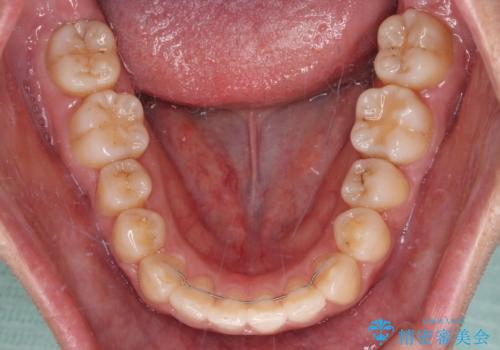

なお、右奥の歯が180度回転した状態で萌出しており、こちらは改善困難なため、そのままの向きで配列することとしました。

右奥の歯が180度回転していることで、噛む度にワイヤーに無理な力がかかったようで、頻繁にワイヤーが切れてしまいました。また、下顎を後方に移動させるためのアンカースクリューも脱離することが多く、治療期間が長くなってしまいました。